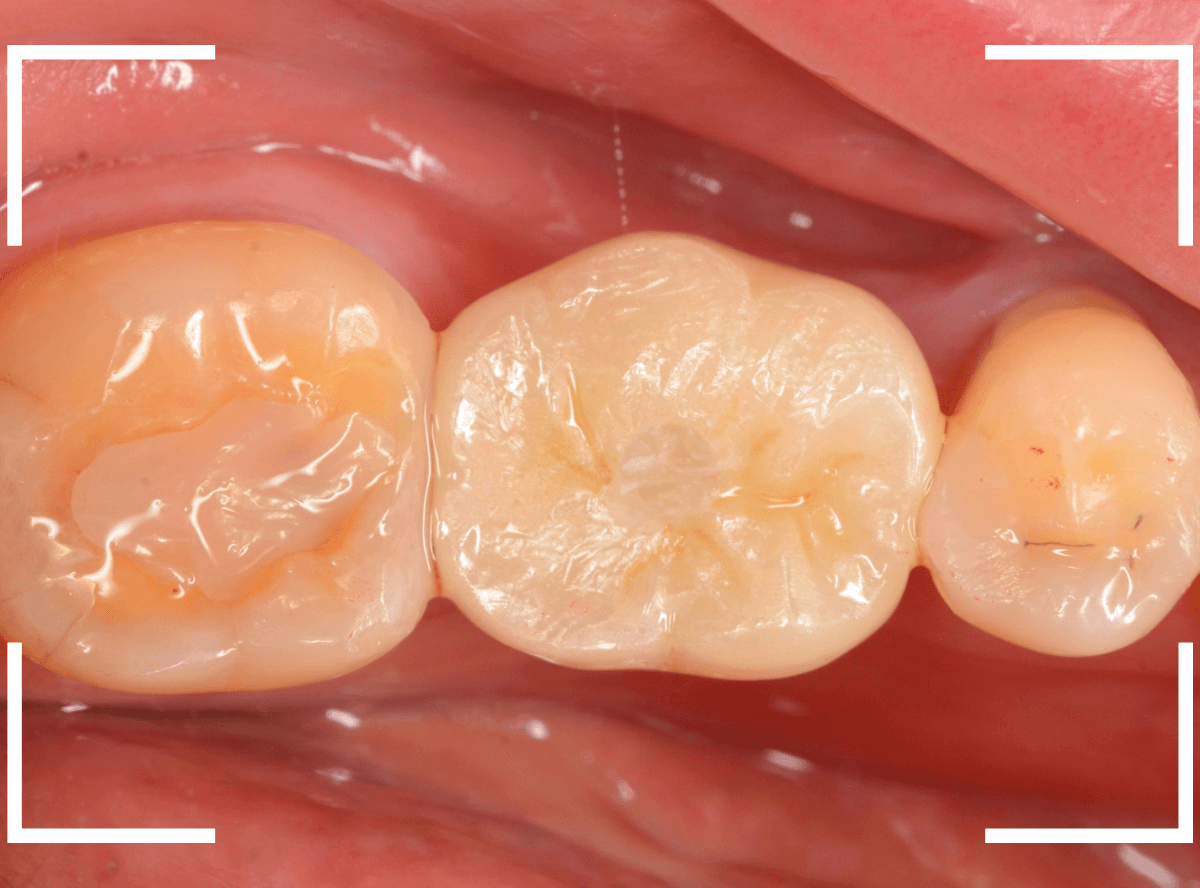

インプラントset後の状況です。

審美的にも、満足いただける仕上がりになりましたが、現在の状況を維持するために治療後の定期メンテナンスが不可欠になります(インプラントに限りませんが)。